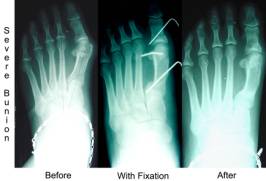

If your IM angle is over 14 degrees we call this a severe bunion. This usually requires work to be done at the base of the metatarsal. We can reduce the IM angle to almost zero depending on the structure of the rest of the forefoot.This requires you not to walk on the foot for a period of 6-7 weeks. A combination of procedures may be necessary with severe bunions. We may need to do work at the head of the bunion also.

With all these bunions we evaluate how much the big toe is drifting towards the second toe and we also evaluate the joint itself. Each of these may require a little extra work. If the joint is totally arthritic and cannot be saved then it might have to be replaced with an artificial one. Many of the arthritic joints if caught early enough can be saved or at least not need artificial joints for a more prolonged period of time.

Bunion surgery has come along way over the last 30 years and the recurrence rate had dropped dramatically as long as you properly evaluate the IM angle on the weight bearing x-ray.